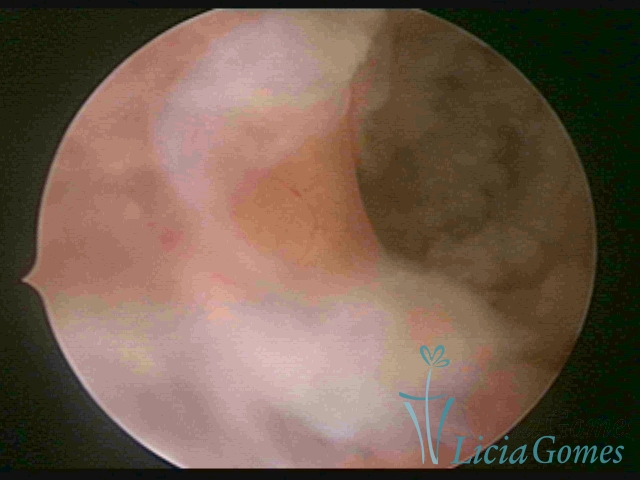

FIBROUS SYNECHIA

• SINÉQUIA TIPO FIBROSA